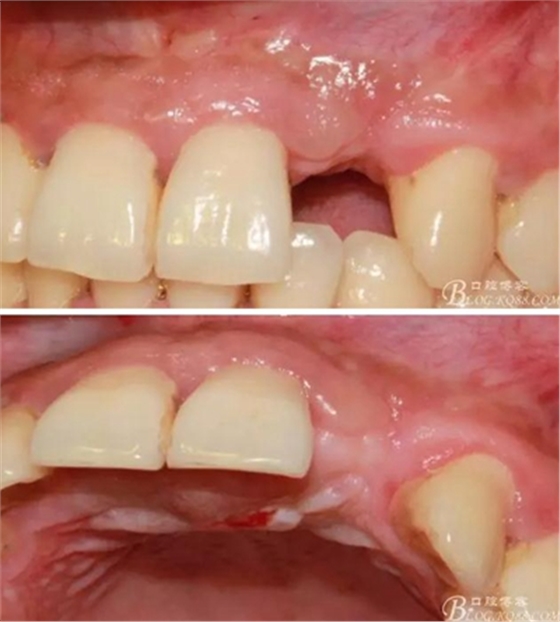

10天拆線一切正常,又過了兩周患者復(fù)診,自述期間無異常??趦?nèi)檢查,真的嚇了一跳,唇側(cè)鼓了個(gè)包,擠壓有白色分泌物溢出,絕對(duì)不是膿液,液體排除后,術(shù)區(qū)觸診空虛,外觀塌陷。這時(shí)候考研大夫的時(shí)刻到了,是先觀察一段時(shí)間再說?還是馬上進(jìn)行處理?我的回答是:馬上處理!如果你沒有及時(shí)處理,而是放患者回家觀察

于是我果斷告知患者,手術(shù)失敗了,不能拖延,如不及時(shí)處理,炎癥繼續(xù)發(fā)展會(huì)很快波及鄰牙牙槽骨?;颊呓邮芪业慕ㄗh。切開翻瓣,骨粉及生物膜消失了,骨吸收嚴(yán)重,幸運(yùn)的是,因?yàn)樘幚砑皶r(shí),鄰牙骨支持依然存在。

事實(shí)證明,我的做法沒有錯(cuò)誤,一個(gè)月后,軟組織健康愈合。鄰牙軟組織沒有退縮。

4個(gè)月后,唇側(cè)豐滿度尚可,與鄰牙之間齦乳頭完整。